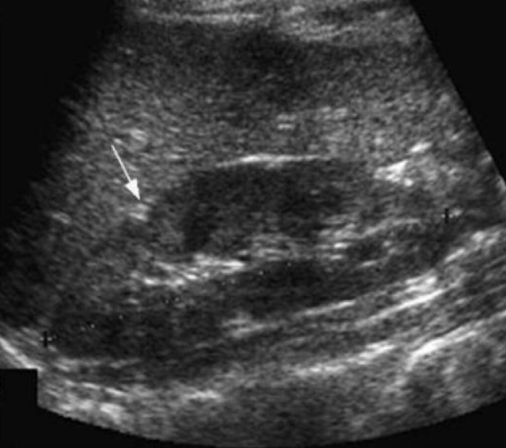

What is the arrow pointing to? A small hyperechoic triangle

Junctional Parenchymal defect

What is the arrow pointing to: